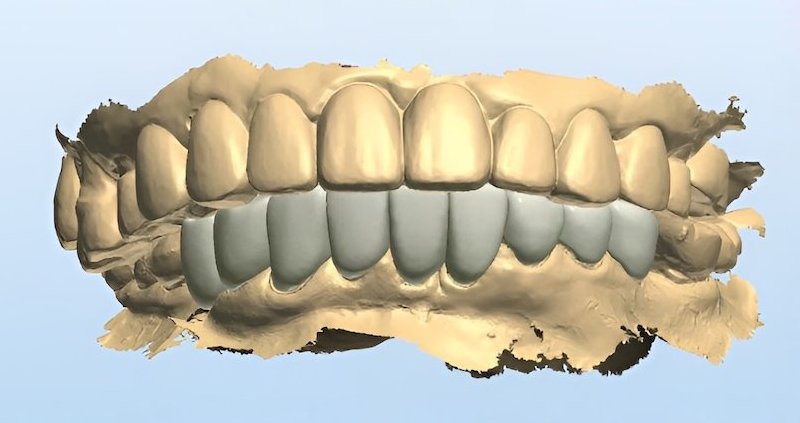

牙周治療過後的美容重建才是高難度的任務。幸好我們現在有數位化的輔助,能夠在還沒修牙齒、做假牙之前,就先讓患者初步試戴(mock up),體驗看看未來完成時的外貌。此時患者也能回饋自己的想法讓醫師和牙技師暸解,輔助我們在合理的範圍內修改到患者能接受的樣子。

討論定案後,我會依照共同決定的結果來修型,口內掃描後再由數位牙技師進行數位化電腦設計與製作。上顎牙橋是使用全鋯冠,其他牙齒則都使用全瓷貼片,將整體空間做好協調分配,完成之後順利地把所有牙縫幾乎都成功關閉。

上顎問題獲得解決之後,Ms.D 等不及要治療下面的牙齒。同樣的流程,我們也順利把下顎的全瓷貼片完成。

試戴流程利用複合樹脂置放在牙齒上,和患者溝通外型。如果有出現比較黃的牙齒顏色,代表牙齒本身位置比較突,這種情況牙齒會需要修得比較多一些,未來才有辦法同時改變牙齒的顏色和視覺上的排列位置: